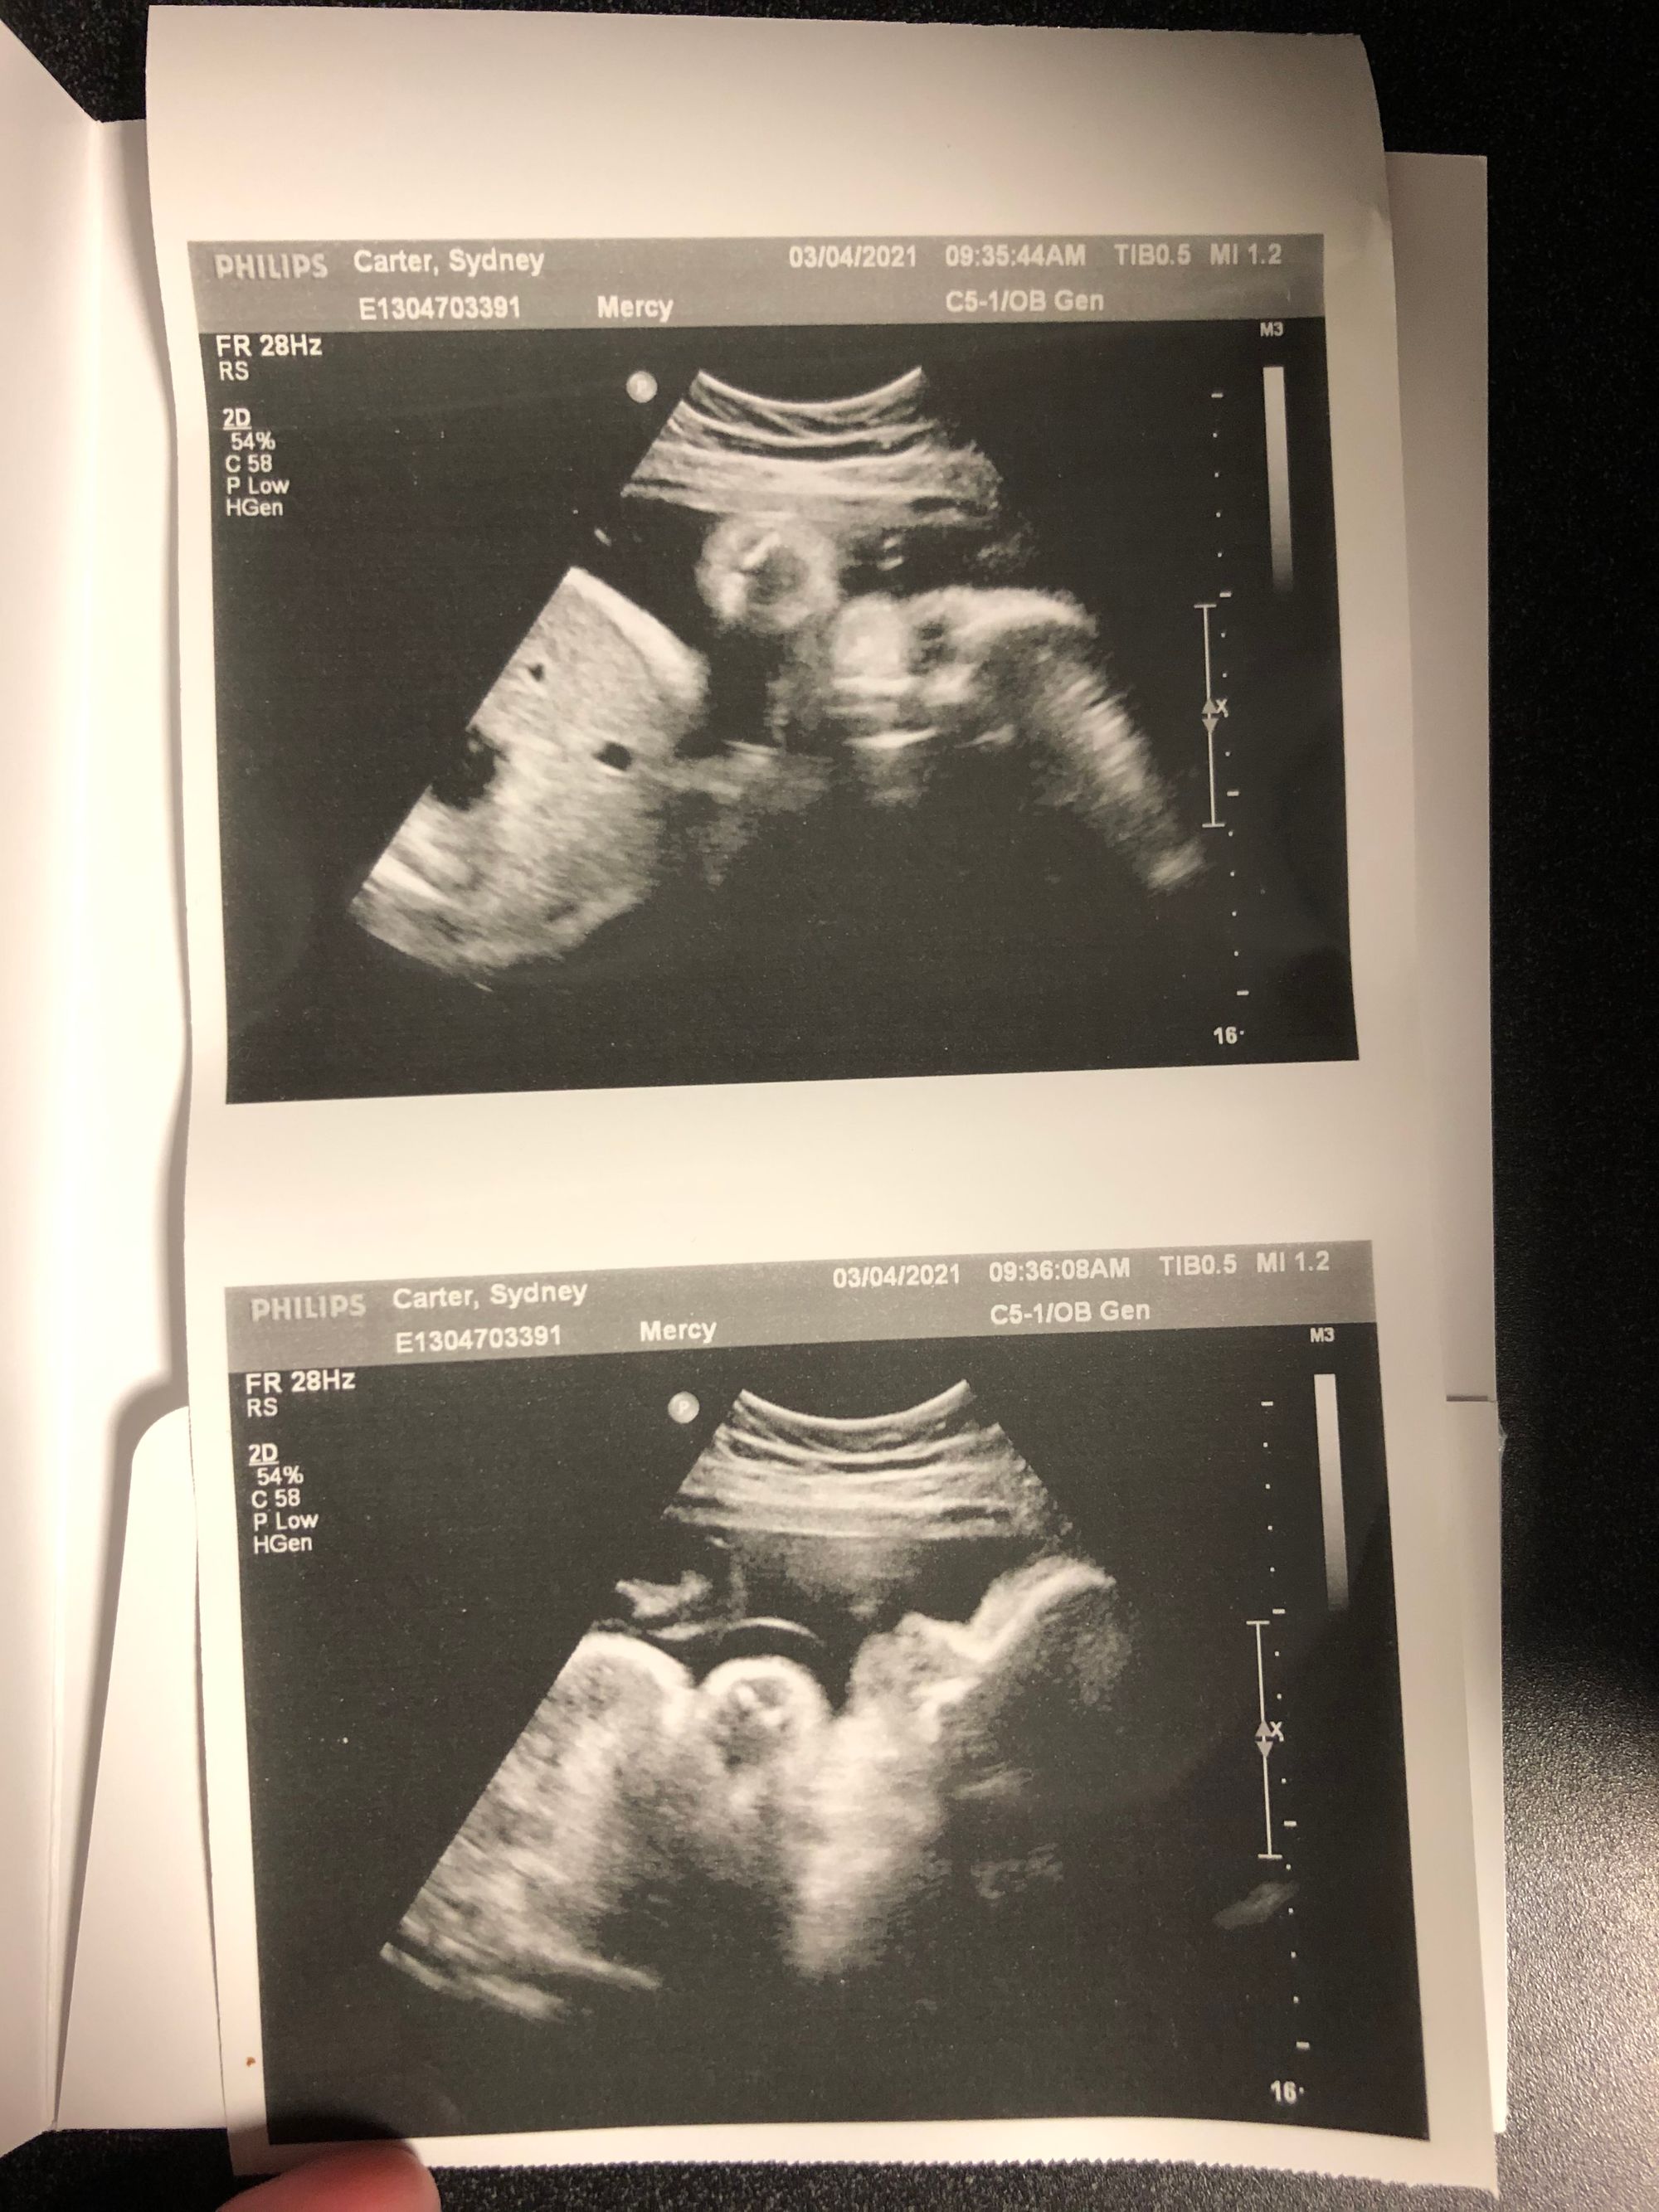

I am still going to the hospital twice a week to do a NST and an ultrasound for fluid levels. It's been pretty uneventful! The tech today told me he has a lot of hair. Yay!

Our final NST + ultrasound!!!